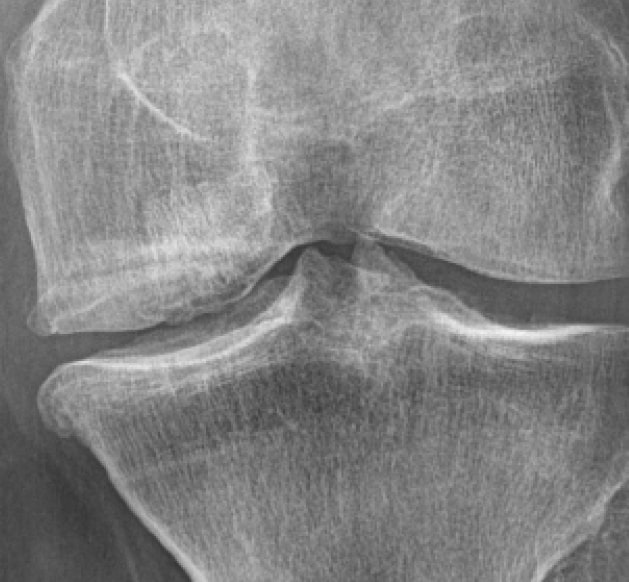

Röntgenbild präoperativ

Tiefer Defekt am medialen Femurkondylus des linken Kniegelenks.